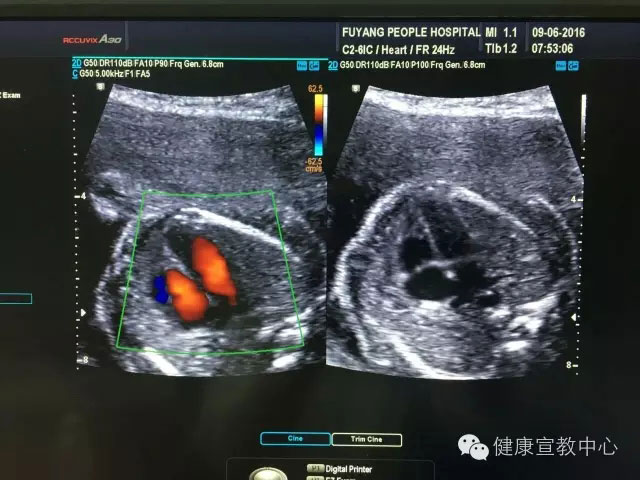

(胎兒超聲心動圖)